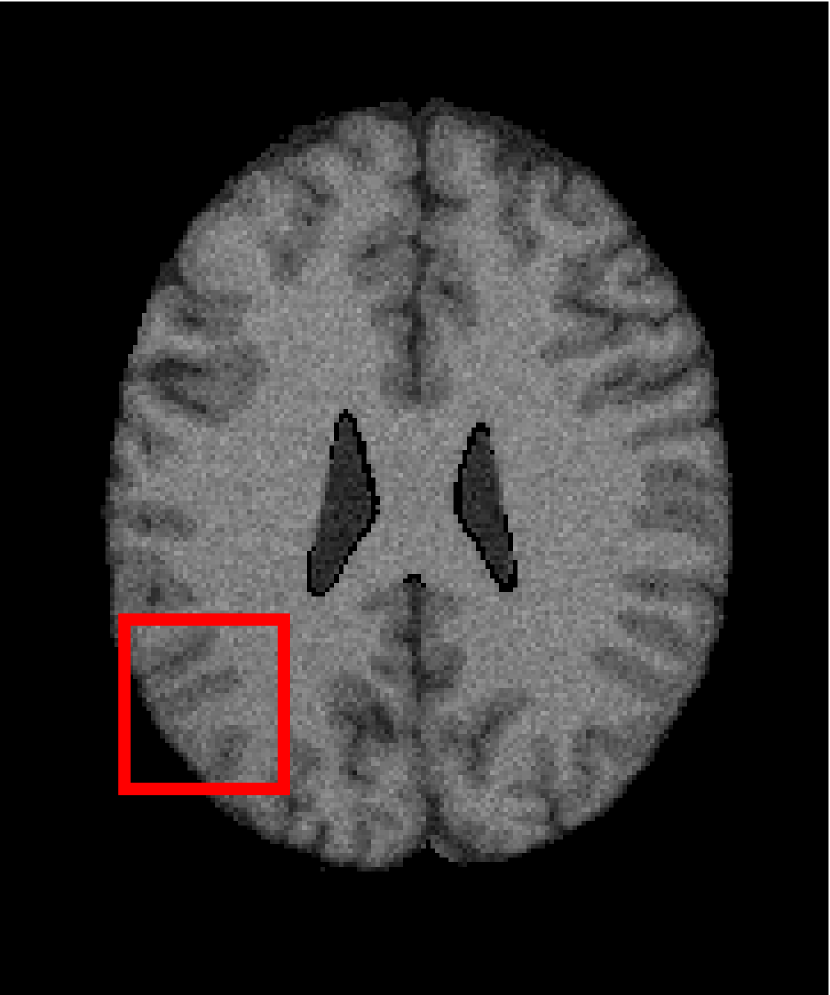

Next, we representatively segment five medical images from BrianWeb. They are represented as five slices in the axial plane with a sequence of 70, 80, 90, 100 and 110, which are generated by T1 modality with slice thickness of 1mm resolution, 9% noise and 20% intensity non-uniformity. Here, we set c=4𝑐4c=4 for all cases. The comparison between WRFCM and its peers are shown in Fig. 9 and Table II. The best values are in bold.

Figure 9: Segmentation results on five medical images. The parameter: ϕ=5.35italic-ϕ5.35\phi=5.35. From top to bottom: noisy images, ground truth, and results of FCM_S1, FCM_S2, FLICM, KWFLICM, FRFCM, WFCM, DSFCM_N, and WRFCM.

By a view of the marked red square in Fig. 9, we find that FCM_S1, FCM_S2, FLICM, KWFLICM and DSFCM_N are vulnerable to noise and intensity non-uniformity. They give rise to the change of topological shapes to some extent. Unlike them, FRFCM and WFCM achieve sufficient noise removal. However, they produce overly smooth contours. Compared with its seven peers, WRFCM can not only suppress noise adequately but also acquire accurate contours. Moreover, it yields the visual result closer to ground truth than its peers. As Table II shows, WRFCM obtains optimal SA, SDS and MCC results for all five medical images. As a conclusion, it outperforms its peers visually and quantitatively.